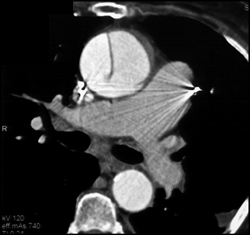

Vascular Bone Removal Algorithm Demo